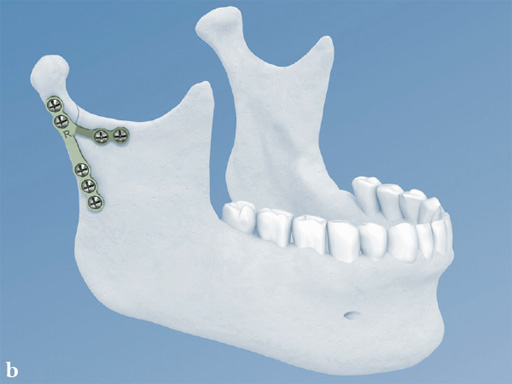

Trapezoidal Plate

The trapezoidal plate is designed to fit the region of the condylar base and provides improved strength and stability over previous single-bar plate designs, thereby eliminating the need to place two plates. It is precontoured to account for the curvature in the transition zone between the base of the condylar process and the adjacent neck. The location of screw holes enables plates to straddle the mandibular foramen and the adjacent canal inlet, thereby avoiding accidental nerve injury. The trapezoidal plate can be applied using external and transoral surgical approaches. If required a transbuccal cannula can be centered in the countersunk screw holes for proper drilling alignment.

Both plates are based on the matrix mandible system platform. Therefore, they are compatible with the existing matrix instrumentation and use the established color-coding for easy identification in the operating room. Both are 1.0 mm thick and malleable (green-grey color coding) and manufactured from commercially pure titanium.